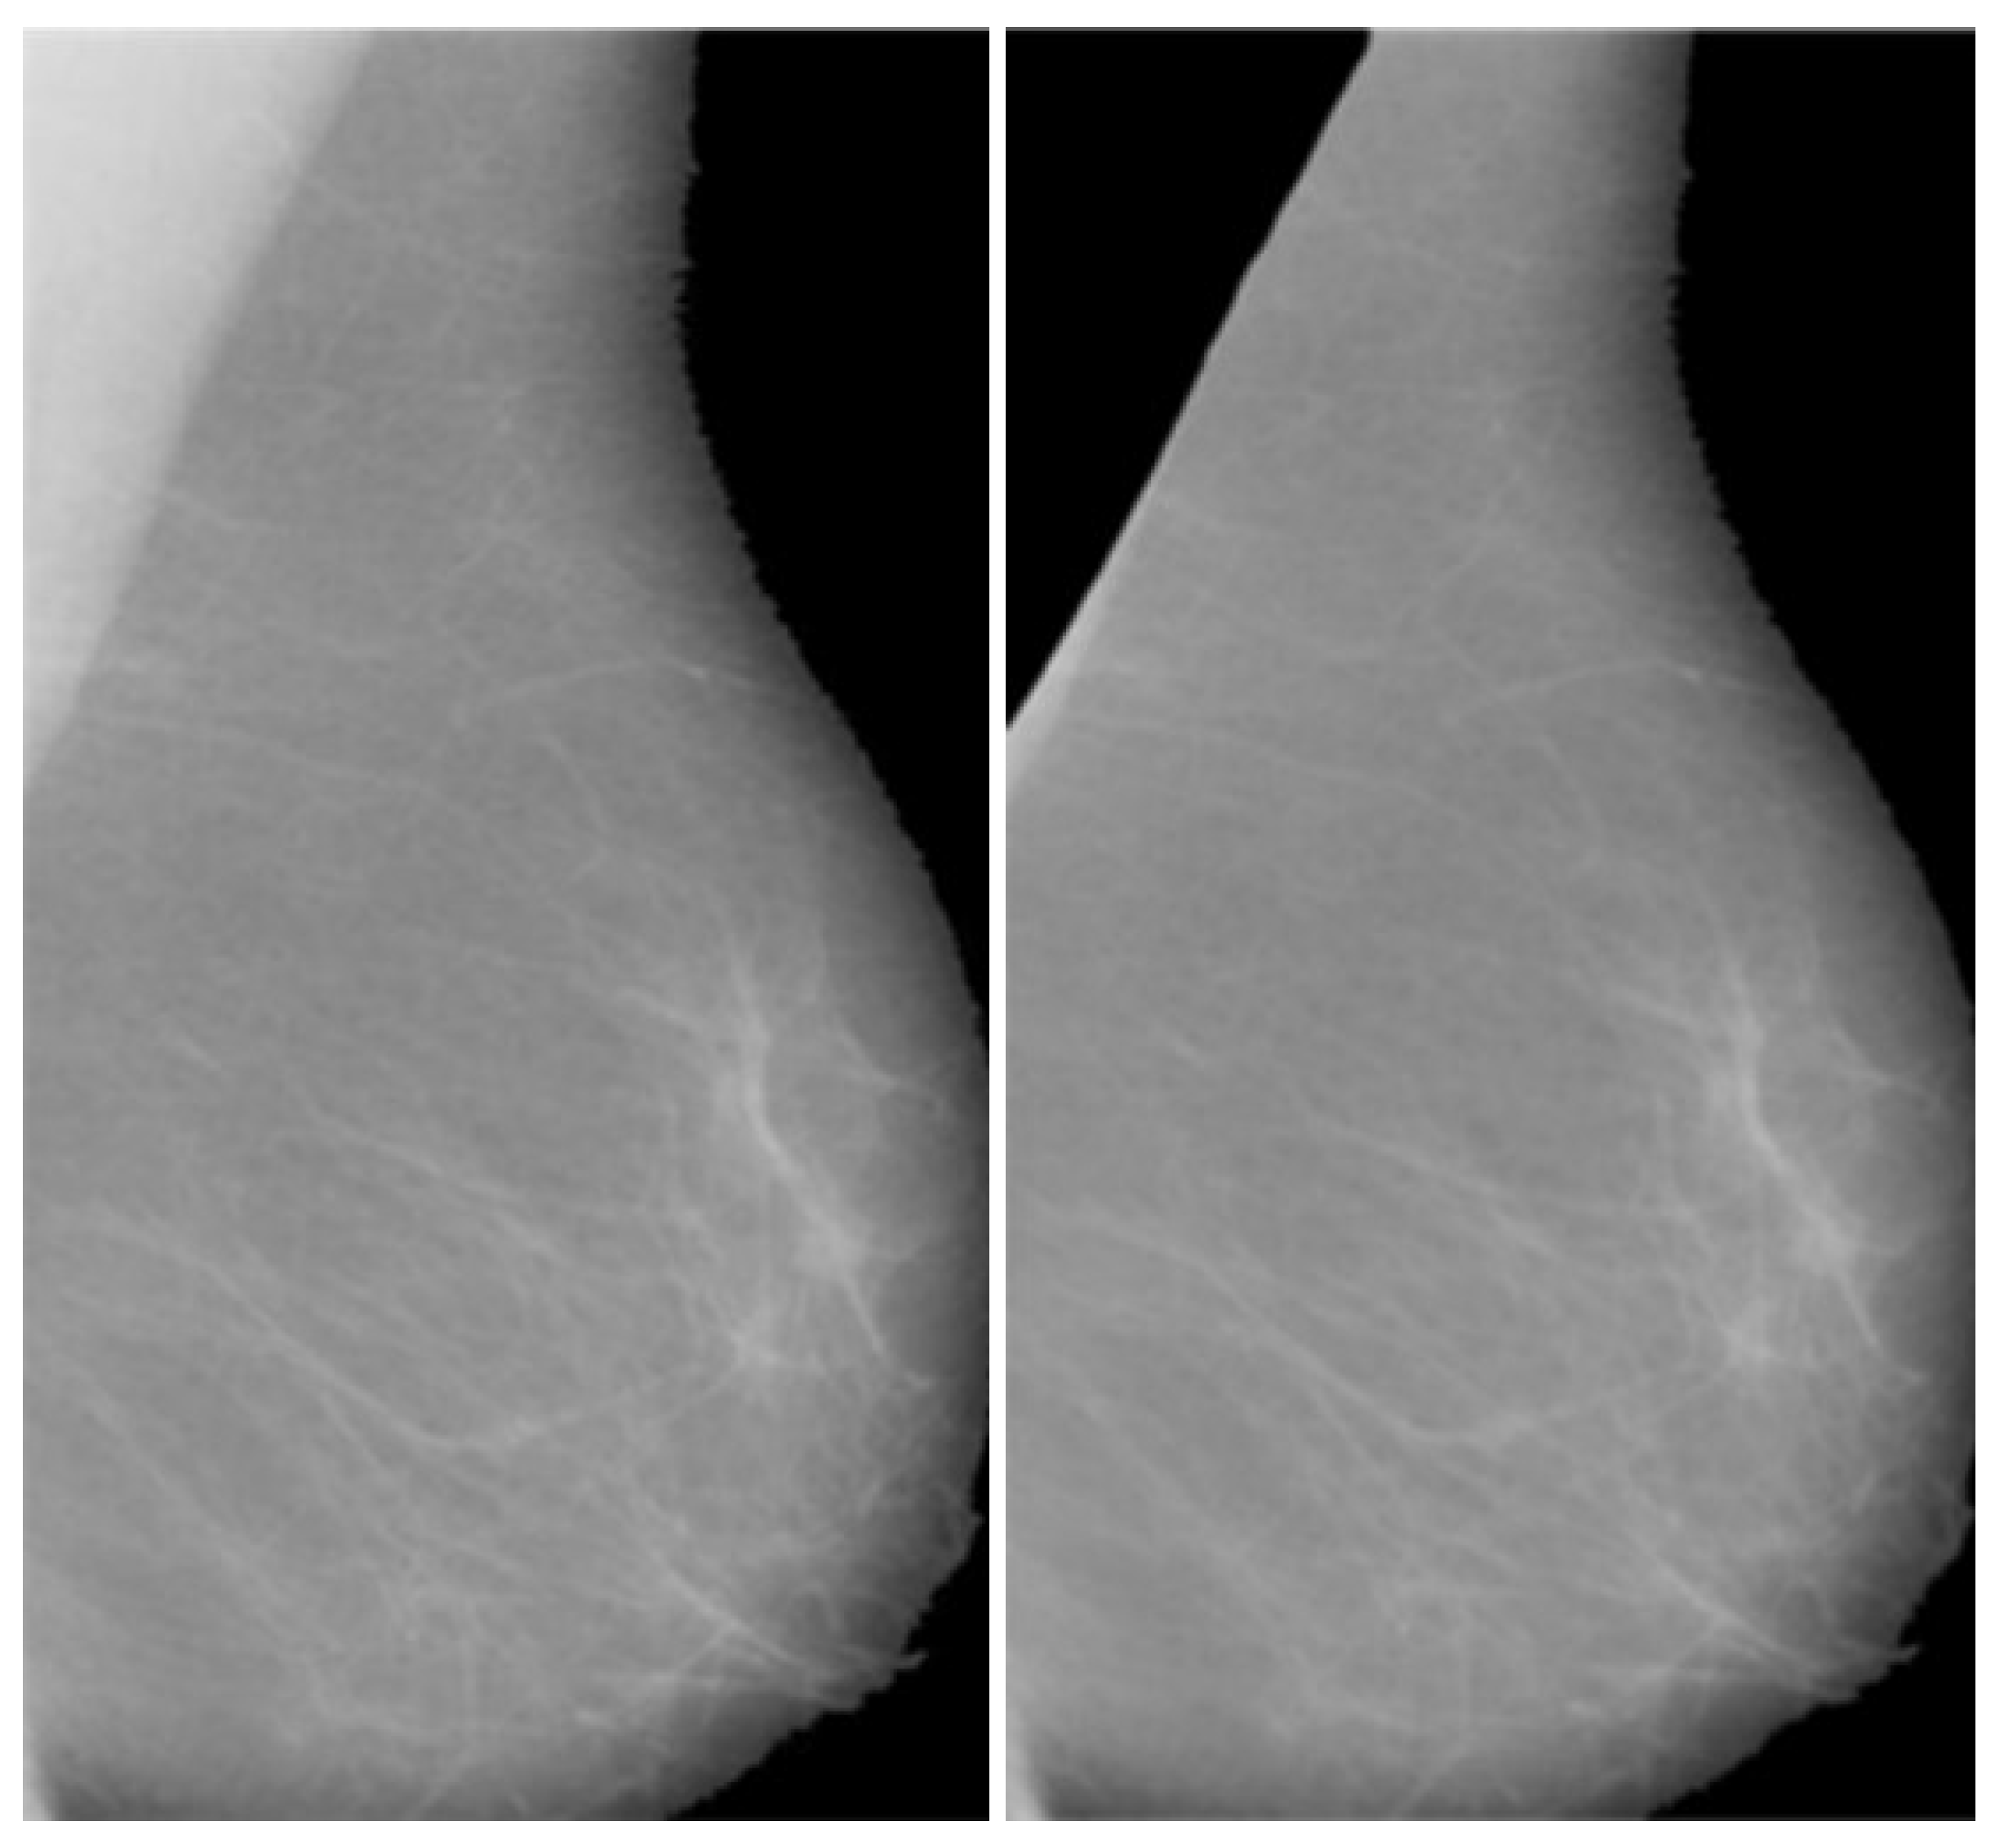

After the classification of the database according to the BI-RADS, the next step was the removal of the pectoral muscles from the images; this was one of the novel steps that improve the efficiency of the overall method. The seed-based region growth technique is used to remove the pectoral muscles in order to obtain the mammary portions of the mammographic images; this area is the region of interest in mammographic images and contains the cancerous region. Seed region growth forms part of the image segmentation technique and contains two types: one type is pixel location value selection, and the other type is seed point selection. The seed point type is more precise and automatically gives an accurate selection based on the orientation of the image. In this proposed method, the starting point is used, which automatically selected the orientation of the mammographic images. The seed points were obtained by using the neighboring seed pixels and it was determined whether the required pixels should be added to or removed from the region. This process was continuous and iterative in nature until the segmentation of the breast region or removal of the pectoral muscle was achieved. The output of the pectoral muscle is removed in Figure 2 and provided an opportunity to analyze the breast area as well as to assist in the enhancement and segmentation techniques.

Figure 2. Final Breast image after pectoral muscle is partially removed.